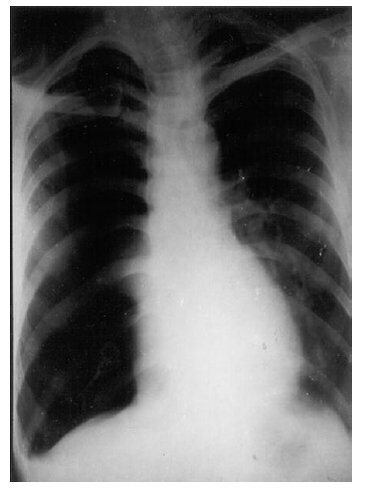

In any x ray start by looking for hyperlucency, absence of lung markings, visceral pleural margin and any fluid level. For example look for figure 1 and analyze the following: Once pneumothorax is recognized, a careful look at x ray may reveal a lot of information about the cause, associated conditions and unravel about underlying lung. 4 However, when we recognizes the presence of pneumothorax we must have a streamlined approach for that. An approach is suggested below. 'Drill' for seeing an X-ray with pneumothorax:

Clinical clue: crepitus in the muscle planes overlying the surgical emphysema. The most obvious finding in this Chest X ray in figure 4 cavity outside the pleura. The hyperlucency is situated lateral to the margin of the collapsed lung (outlined by the visceral pleura). Therefore this hyperlucency is clearly due to presence of free air in the pleural cavity. The simultaneous presence of air and fluid indicated by a horizontal fluid level, helps to identify this situation as a hydropneumothorax. Note that the visible portion of the partially collapsed lung is not healthy-there is an apical cavity. The opposite lung also shows evidence of infiltration. The overall picture strongly suggests possibility of underlying tuberculosis as evidenced by the cavity, whose rupture is most likely the cause of pneumothorax.